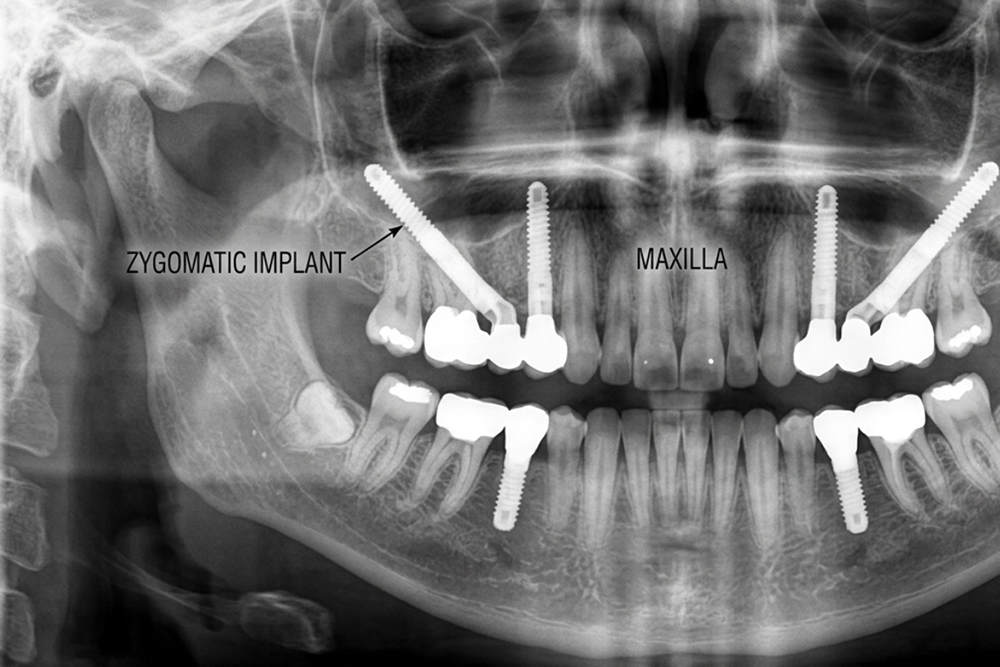

Zygomatic dental implants are longer, specialized implants that anchor in the cheekbone (zygoma) rather than the jawbone. This innovative approach bypasses the need for adequate jaw bone entirely.

- Angle: Placed at a specific angle through the upper jaw

The zygomatic bone (cheekbone) is a dense, reliable structure. It maintains its density even when the upper jaw has experienced significant resorption. This makes it an excellent anchor point for dental implants.

Zygomatic dental implants pass through the remaining upper jaw bone and anchor firmly in the cheekbone. The dense cheekbone provides exceptional stability for the implant.